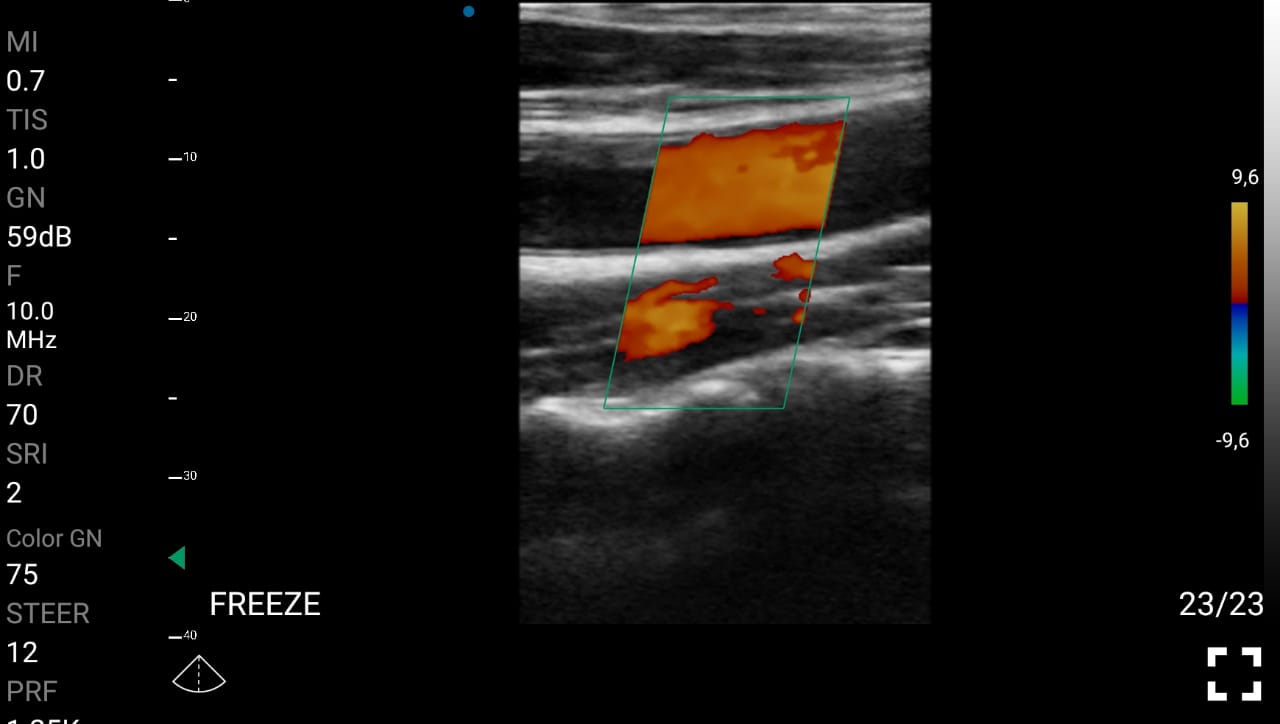

• Ανίχνευση αθηρωματικών πλάκων και στενώσεων: Η υπερηχογραφία, μέσω της μεθόδου Doppler, μπορεί να βοηθήσει στον εντοπισμό αθηρωματικών πλάκων ή στενώσεων στα αγγεία, ιδίως στις καρωτίδες, τις μασχαλιαίες, τις λαγόνιες και τις λαγόνιες αρτηρίες.

• Αξιολόγηση της ροής του αίματος: Η υπερηχογραφία Doppler παρέχει άμεσες πληροφορίες για τη ροή του αίματος σε διάφορες περιοχές του σώματος, προσδιορίζοντας τις περιοχές που χρήζουν επεμβατικής αποκατάστασης.

Παραδείγματα

Ολες οι παραπάνω απεικονιστικές εξετάσεις έχουν ληφθεί από φορητή συσκευή όπως: Apple Iphone, Tablet, Samsung Mobile Phones και διάφορες άλλες φορητές συσκευές.